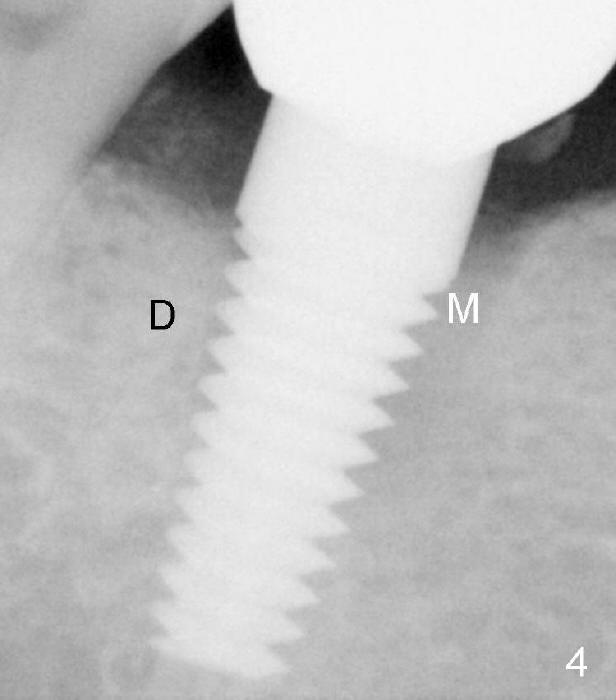

Fig.4: PA taken prior to 2nd bone graft (13 months post 1st one). It appears that the distal bone loss has been fixed by the 1st bone graft, while the mesial one remains the same. There is no symptom or sign of periimplantitis 3 years 8 months post 2nd bone graft (Fig.7 previous mesial defect having been repaired).